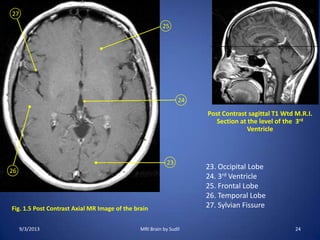

Fig. 1.5 Post Contrast Axial MR Image of the brain

23

24

25

26

27

Post Contrast sagittal T1 Wtd M.R.I.

Section at the level of the 3rd

Ventricle

23. Occipital Lobe

24. 3rd Ventricle

25. Frontal Lobe

26. Temporal Lobe

27. Sylvian Fissure

9/3/2013 24MRI Brain by Sudil